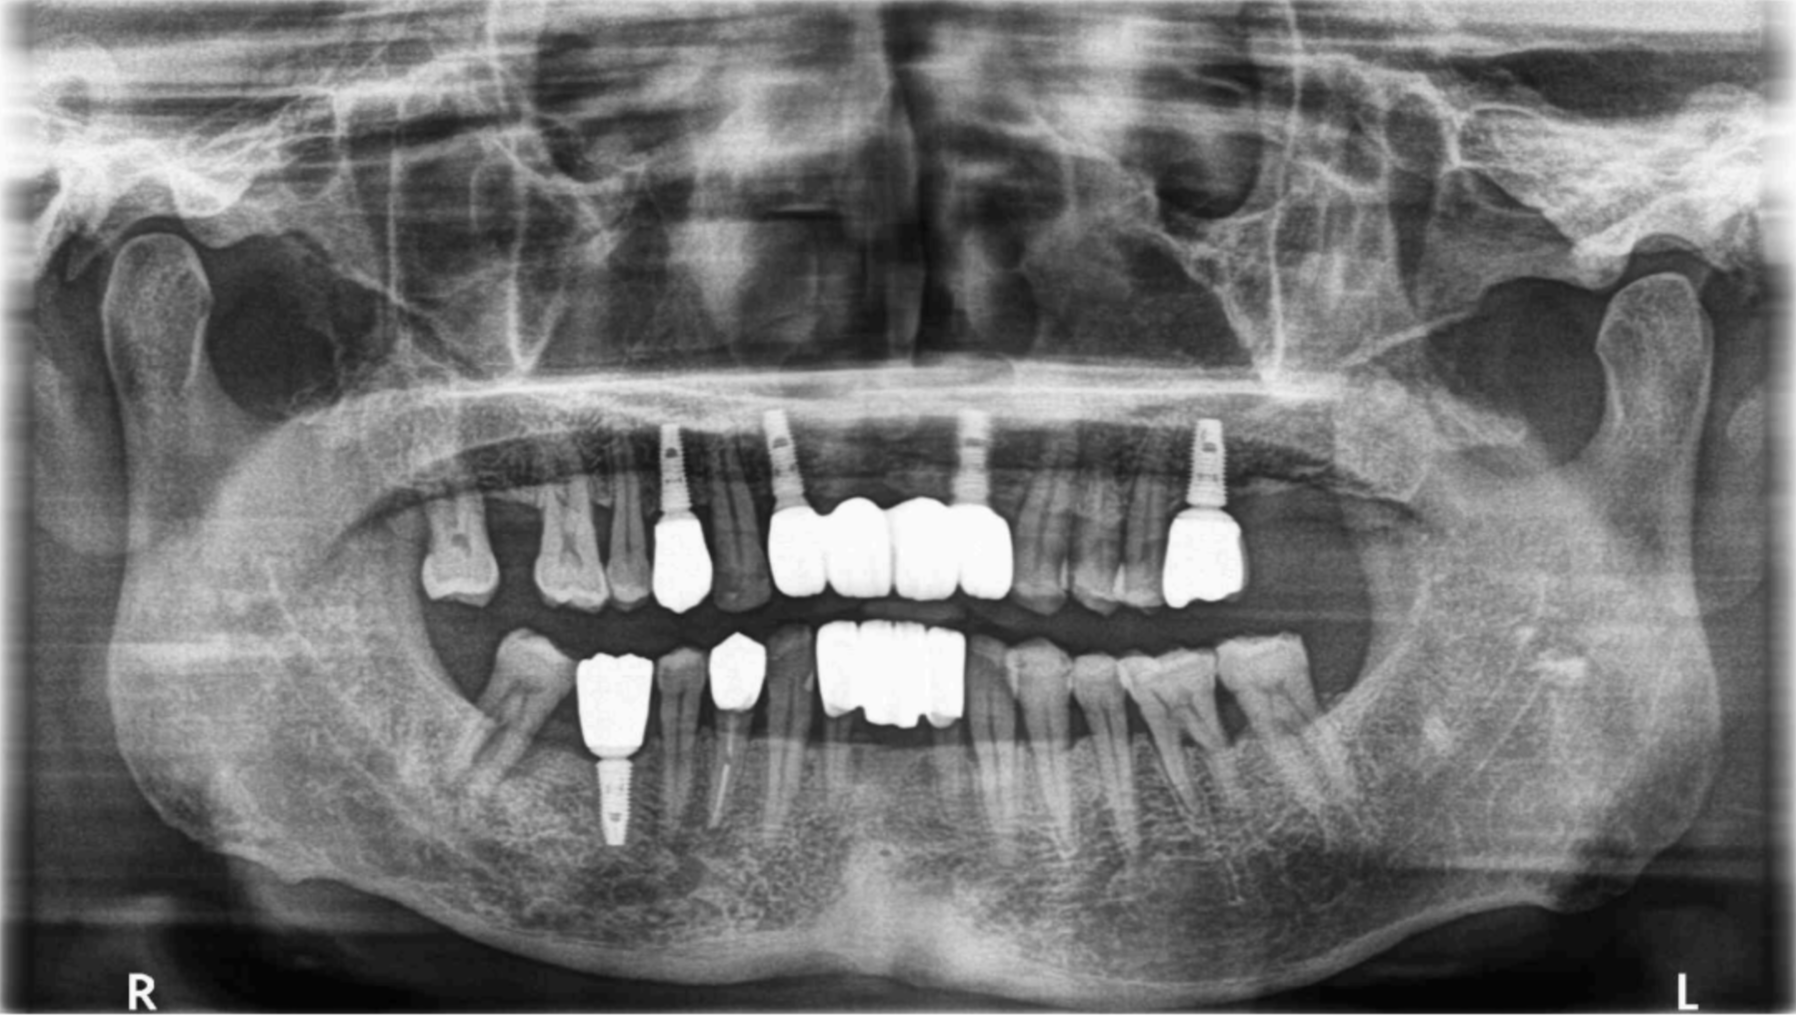

【全口重建:全口磨耗和缺失後牙支撐】 【治療醫師:林農翔 醫師】 黃先生因為前牙假牙搖動無法進食而走進診間,經過電腦斷層和照相檢查判斷,告訴他現在牙齒會有現在的 …